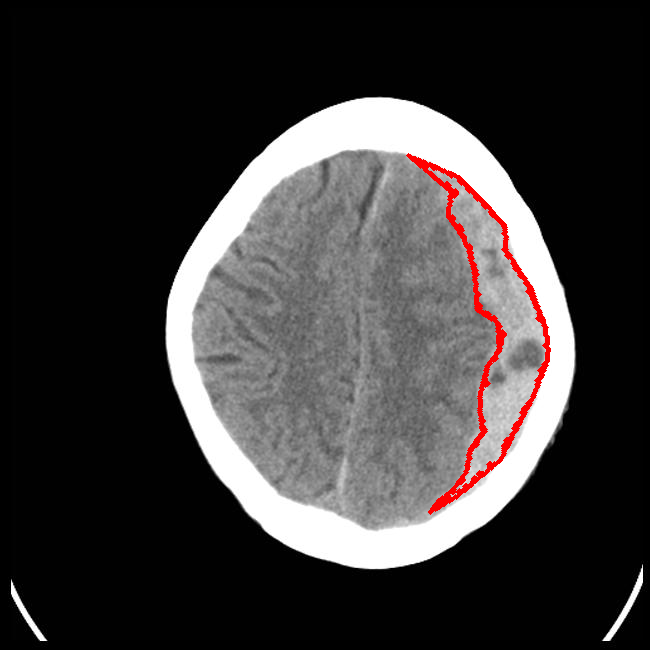

Limited Angle

CT GMAIMMbench Disease Diagnosis

Limited Angle - L0 (Original)

L0

L0 (Original)

Limited Angle - L1 (Moderate)

L1

L1 (Moderate)

Limited Angle - L2 (Severe)

L2

L2 (Severe)

Question

This is a CT image. Which of the following options is the most appropriate to demonstrate the marked area?

A brain hemorrhage B barrett's esophagus C thyroid nodule D retinal hard exudates

Ground Truth: A. brain hemorrhage